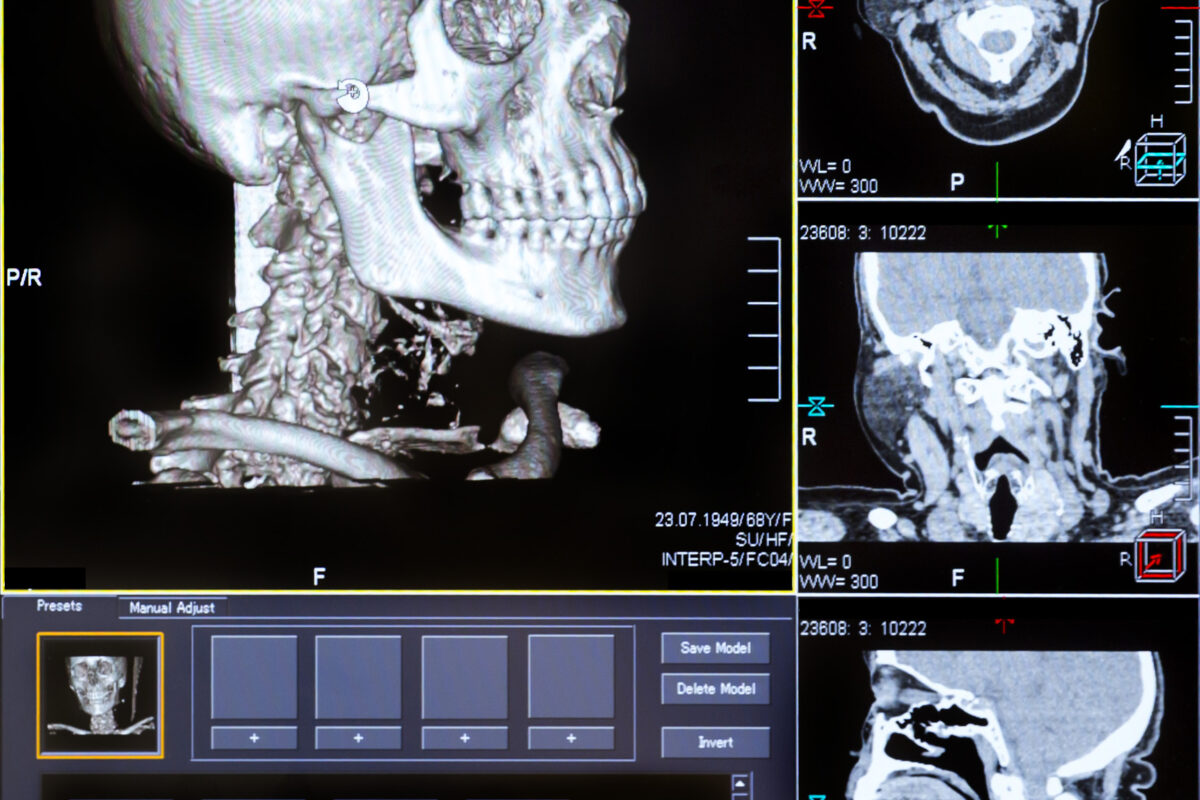

X-ray and CT Imaging: Balancing Dose and Diagnostic Yield

X-ray and computed tomography (CT) imaging remain the workhorses of diagnostic radiology. They provide rapid and detailed anatomical information, particularly valuable in emergency and oncological settings. However, both modalities involve ionising radiation, which carries inherent risk.

Optimising imaging protocols involves fine-tuning parameters such as tube voltage, current, exposure time, and slice thickness. Techniques like automatic exposure control (AEC) and iterative reconstruction algorithms enable personalised radiation dose while maintaining or enhancing image quality. In paediatric imaging, dose reduction strategies are particularly important due to the increased radiation sensitivity of children.

Advanced detector technologies and dual-energy CT (DECT) now offer improved tissue characterisation and contrast resolution without requiring higher doses. Protocol standardisation and regular quality control are also essential in ensuring consistent image quality across different scanners and institutions.